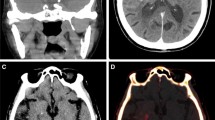

In 10/16 patients with EST of large intracranial arteries and immediate post-interventional DECTs (100/140 kV), residual peripheral clots were found on the digital angiography series on the BW, VNC, and IM protocols. Arteries with clot material were identified in 9/10 cases on the VNC only, while the absence of clots was correctly rated in 5/6. Arteries with clot material were significantly denser than perfused arteries on the VNC only (Fig. 4) [42].

Contrast-enhancing areas on DECT (100/140 kV) immediately after EST in 132 patients were found in 32 and hemorrhage in 53 patients. Follow-up imaging was either CT or MR imaging. Subjective assessment by an uncertain amount of raters revealed both contrast enhancement (odds ratio (OR) 11.3) and hemorrhage (OR 10.4) to be associated with a poor clinical outcome (modified Rankin scale 3–6), even if complete recanalization was achieved. In addition, patients with contrast-enhancing areas displayed a higher rate of delayed hemorrhagic transformations (OR 4.5) [38]. To investigate under which circumstances contrast-enhancing areas would transform to infarctions or delayed hemorrhage, the DECT scans (100/140 kV) of 20 patients with 44 contrast-enhancing areas who underwent EST were analyzed and ROI density measurements were performed on BW, VNC, and IM imaging by two raters, withhigh inter-rater reliability. Areas that transformed to infarctions revealed higher densities on IM, representing a higher amount of contrast enhancement (Fig. 3), with a cutoff value of 34.1 HU, compared to areas that did not transform (area under the curve (AUC) 0.99). For the prediction of delayed hemorrhage, the AUC was 0.78 [39]. On the DECT (80/140 kV) images of 85 patients immediately after EST, maximum iodine concentration was measured by two raters, if iodine staining was present (n = 54). In areas with an iodine concentration > 1.35 mg/dl, later development of hemorrhage was more likely, with an AUC of 0.89 [40].

Brain window (a, d), iodine map (b, e), and diffusion-weighted follow-up MRI (c, f) series. The upper row shows a slight iodine staining in both thalami and the right occipital lobe on the brain window and the iodine map series, with no future infarction; the lower row shows more pronounced iodine staining in both thalami and the right upper cerebellum, with later infarction development